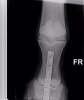

Что касается лечения, то при таких переломах оно также может быть консервативным (полный покой, ортопедическая ковка и/или гипсовая повязка) или хирургическим. При выборе метода лечения врач учитывает тип и место перелома; породу, размер и темперамент лошади, а также ее будущее предназначение. Так, продольные одиночные внутрисуставные трещины или простые переломы в путовой кости имеют гораздо лучший прогноз на восстановление после хирургической фиксации (остеосинтеза). Такая операция проводится под общим наркозом и заключается в фиксации сломанных кусочков костей при помощи специальных пластин и шурупов. При своевременной и удачной операции большинство животных возвращаются к нагрузкам и имеют все шансы работать и не хромать.

Одним из последних ветеринарных достижений при лечении переломов у лошадей, является метод транскортикальной (чрезкостной) фиксации. Смысл такой фиксации заключается в том, что выше места перелома внутри кости временно ставят специальные металлические стержни, а потом всю конечность одевают в легкий и вместе с тем очень прочный полимерный гипс, в котором и закрепляют эти стержни. Таким образом, получается, что конечность лошади выше места перелома как бы подвешивается внутри гипсовой повязки. В результате этого лошадь получает возможность полностью опираться на сломанную конечность, так как весь ее вес при этом ложится только на здоровую кость и гипс, а поврежденный участок остается без нагрузки. Устанавливаются такие стержни под общим наркозом, как правило, одновременно с наложением гипса или при проведении операции по остеосинтезу. В настоящее время метод уже достаточно широко апробирован как за рубежом, так и у нас и помог спасти не одну лошадиную жизнь. Во многом, только благодаря транскортикальной фиксации у врачей появился шанс бороться за жизни лошадей даже при таких серьезных травмах, как полный перелом пястной или плюсневой костей.

Стоял с гипсом 2,5 месяца, постоянные рентгены, жрал кучу всего. Гипс он как-то так продавил пяткой или что еще сделал, но получился, как костыль, на который он мог опираться и как-то даже перемещался по деннику. Сразу научился ложиться, вытягивая ногу и также вставать. Он сразу хотел жить и делал всё от него зависящее. Вот в этот период у него было отличное дыхание, что вообще никто не может объяснить.

Реабилитация заняла год. Период начала и середины шаговки был увлекательный Хозяйка конюшни только могла с этим справиться )))

На месте сращения отломков образовалась шишка, предупредили, что это жабка (вроде так) и она может расти дальше.

Лошадка имеет свои особенности сейчас по поддержке артроза. Но не ужас-ужас. Как обычный хроник по ногам. Хобл доставляет гораздо больше хлопот. Живет полноценной жизнью. Играет, пинается, порой при его хорошем настроении может показать всаднику в поле, что 15/16 крови чк это не хухры-мухры Он просто офигенный по мозгу, темпераменту и характеру.